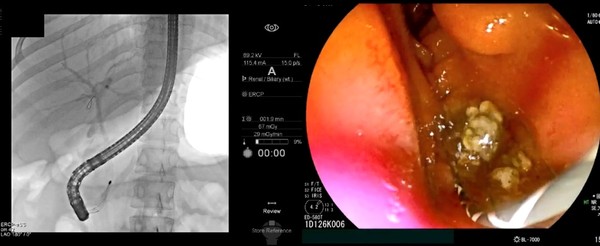

초음파내시경으로 담관결석이 관찰되면 내시경적 역행성 담췌관조영술(이하 ERCP)을 통해 담관결석을 제거한다. ERCP는 특수내시경과 방사선을 이용한 시술로, 내시경을 십이지장까지 삽입하고 십이지장 유두부를 통해 담관에 관을 넣고 조영제를 주입해 담석의 정확한 위치를 확인한다. 이후 미리 넣어놓은 가이드선을 따라 바스켓 또는 풍선 기구를 담관으로 넣어 담석을 제거한다. ERCP로 담관결석을 제거한 뒤에도 재발을 막기 위해 담낭담석을 제거하는 담낭절제술이 필요하다.

ERCP는 개복 등 수술적 치료 없이 내시경시술을 통해 담관결석을 제거할 수 있지만 시술 난도가 높고 침습적 치료이기 때문에 드물게 부작용과 합병증이 발생할 수 있다. 특히 십이지장 유두부가 매우 좁아 결석을 빼내기 위해 유두부 괄약근을 절개하는 과정에서 출혈이나 천공 등의 위험이 있다. 가장 흔한 시술 관련 합병증은 췌장염이며, 대부분은 경증이나 심각한 경우 중증도의 췌장염이 나타날 수 있다. 그럼에도 불구하고 ERCP는 수술 없이 시술만으로 담관결석을 제거할 수 있고 비교적 신속한 치료가 가능하다는 장점이 더 크다.